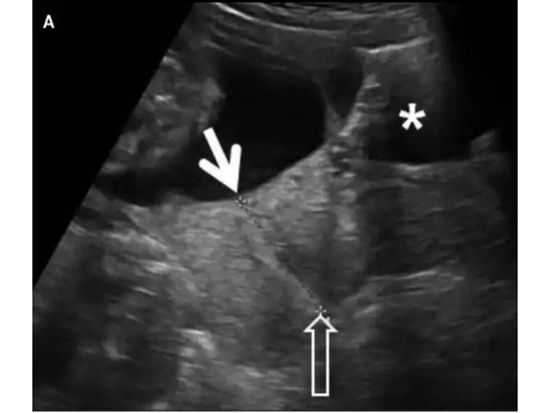

- 特殊形态:如果超声发现羊膜囊向宫颈管内突出,甚至部分胎囊膨入,是宫颈功能不全的典型表现。